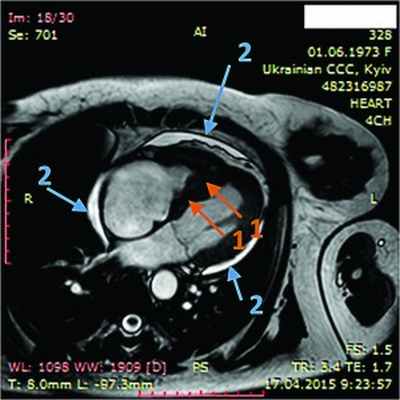

При рентгенологическом обследовании органов грудной клетки обнаруживают кардиомегалию и признаки венозного застоя в легких. Изменения ЭКГ не специфичны. Частые находки – нарушения ритма сердца, особенно фибрилляция предсердий (ФП). В диагностике заболевания основную роль играет эхокардиография (ЭхоКГ), позволяющая обнаружить локальное (реже – диффузное) утолщение верхушки одного или обоих желудочков с вовлечением в патологический процесс хорд, умеренную митральную или трикуспидальную регургитацию, пристеночные, особенно верхушечный, крупные тромбы. Показательным является «рестриктивный тип» ремоделирования сердца и внутрисердечной гемодинамики – очевидное преобладание объема предсердий над объемами желудочков. Систолическая функция, как правило, сохранена, но диагностируется диастолическая дисфункция – рестриктивный тип трансмитрального/транстрикуспидального кровотока. Наиболее информативными методами исследования на сегодняшний день являются магнитно-резонансная томография (МРТ) и мультиспектральная компьютерная томография с контрастированием 14. В литературе описан случай динамического наблюдения за развитием эндокардита Леффлера с серией одновременно производимой позитронно-эмиссионной томографии и контрастированной МРТ с выделением стадий: бессимптомной, острой некротической, симптомной тромботической и фибротической [13]. Выполнение эндомиокардиальной биопсии миокарда правого (ПЖ) или левого (ЛЖ) желудочка позволяет подтвердить или опровергнуть диагноз эндокардита Леффлера.

14.04.2015 г. пациентка была госпитализирована в Национальный научный центр «Институт кардиологии им. Н.Д. Стражеско» в отделение некоронарогенных заболеваний сердца и клинической ревматологии, где был выставлен (подтвержден и уточнен) диагноз: ГЭС. Эндокардит Леффлера с поражением ЛЖ и ПЖ. Массивные пристеночные тромботические наслоения в ПЖ. Апикальный тромб ЛЖ. Мелкие тромбы в ушках обоих предсердий. Синусовая тахикардия. Единичные желудочковые ЭС. Перикардит с небольшим количеством жидкости. СН IIА ст. со сниженной сократительной функцией ЛЖ ІІ ФК по NYHA. Аутоиммунный тиреоидит, эутиреоз. Токсокароз, висцеральная фаза.

ЭхоКГ: Патологические изменения миокарда ПЖ с утолщением стенок до 18 мм. Диффузный гипокинез стенок ЛЖ с дискинезом верхушки – ФВ 44%. В области верхушки ПЖ – наслоения между листками перикарда. Небольшое количество жидкости в полости перикарда – по ЗСЛЖ до 5 мм. Таким образом, в динамике на ЭхоКГ наблюдалось снижение сократительной функции ЛЖ на фоне его гипертрофии и, несмотря на проведенную высокодозовую терапию гормонами, не уменьшилась гипертрофия ПЖ.

В ходе серии динамических МРТ с контрастированием (рис. 7-11) выявлены массивные пристеночные тромботические наслоения в ПЖ, апикальный тромб ЛЖ.